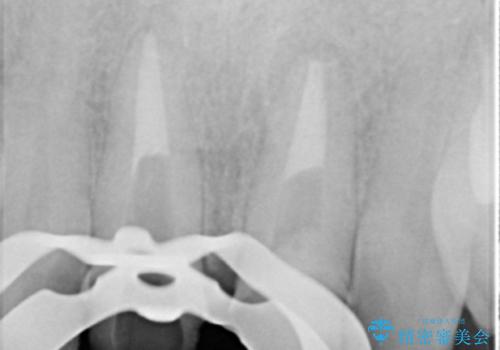

X線写真より、根尖部に透過像が認められ根管治療・ファイバーコア築盛・セラミッククラウンの作製が必要な状態です。

X線検査や歯周組織検査などを行い適切な治療を行うことで良好な結果を得ることができます。